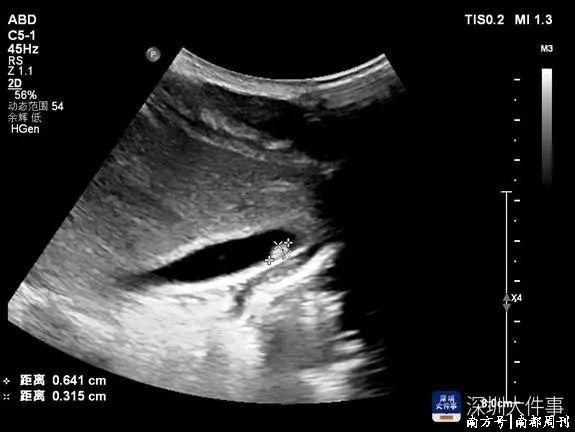

现存的把柄齐指向了寄生虫,在大夫的忽视下,小凯一家三口齐作念了寄生虫磋磨查抄,后果骄贵,三东说念主血成例中嗜酸性粒细胞齐畸形升高!小凯还有肝功能畸形,彩超骄贵肝内有片状低回声区,肝门淋取悦肿,小凯姆妈的大便中检出肝吸虫卵!

这下,小凯反复发热的原因终于找到了,即是肝吸虫病(华支睾吸虫病),可能即是那碟适口的生鱼片导致的。